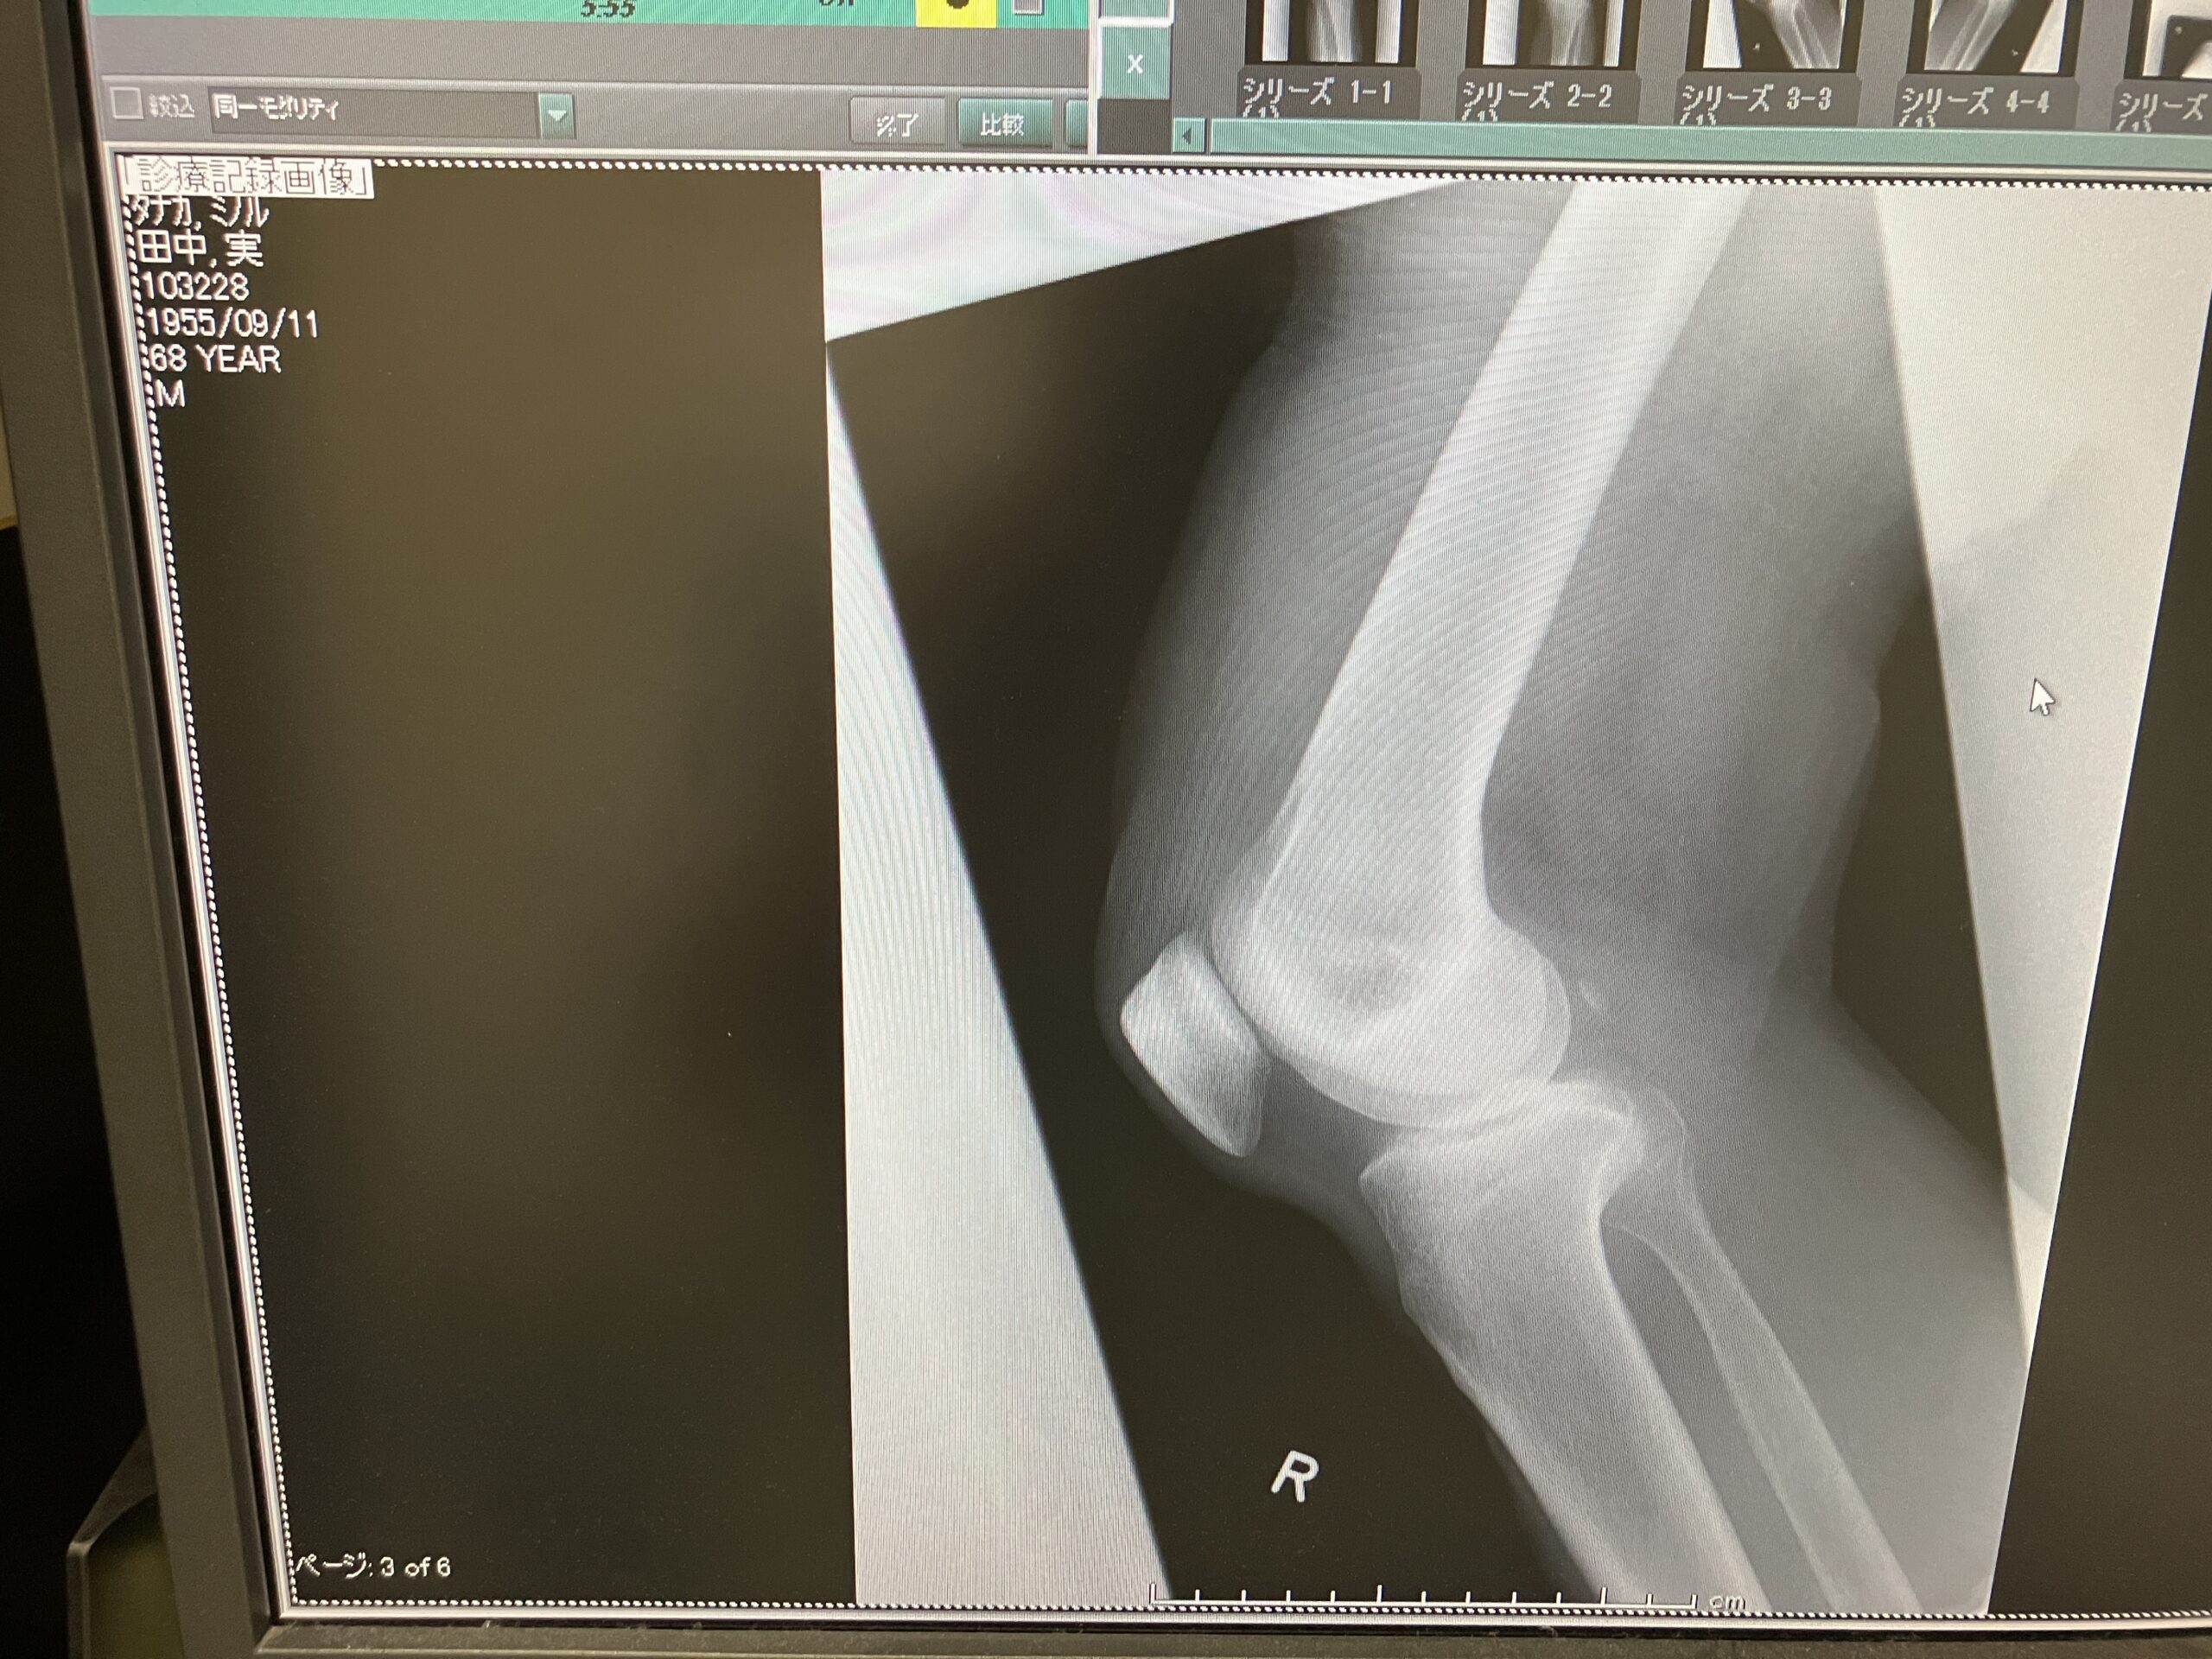

変形性膝関節症